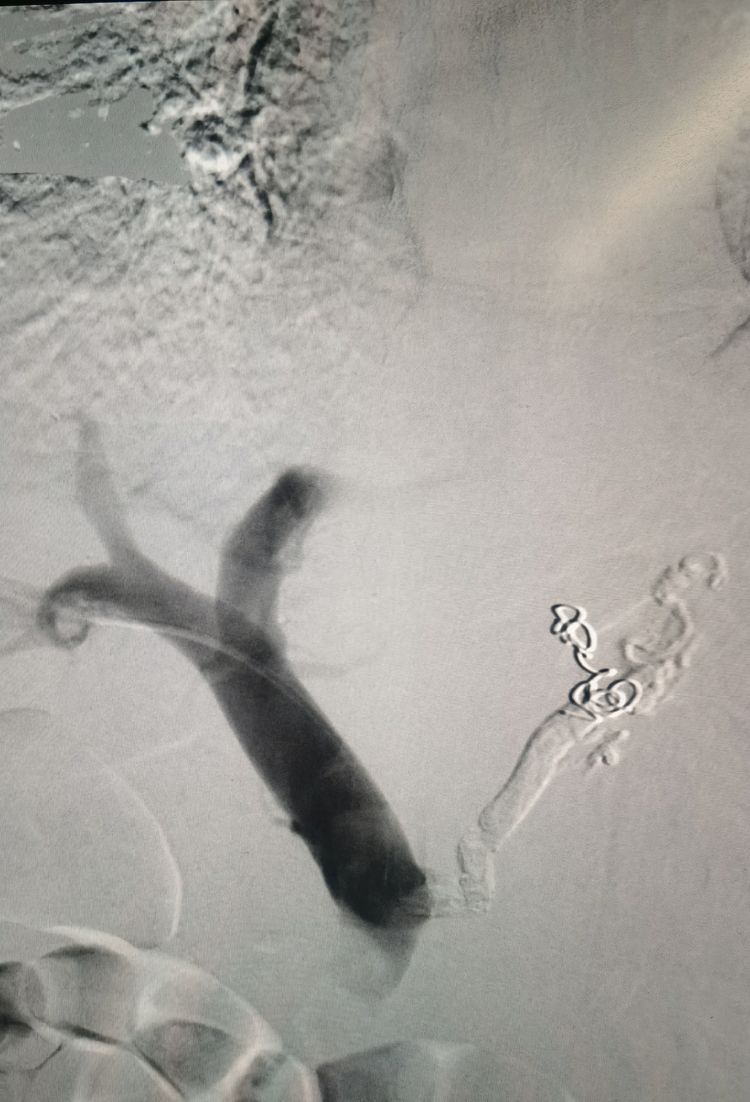

栓塞结束后再次造影:食管胃底曲张静脉消失。术后患者未出现呕血、黑便。